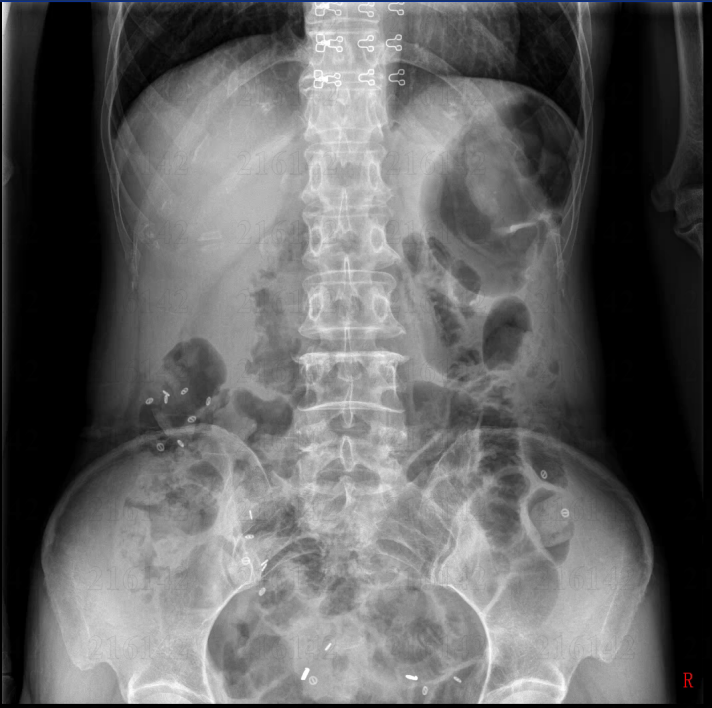

以周女士为例,72小时内即完成结肠传输试验、排粪造影等7项评估,确诊为“慢传输型便秘”合并“泻剂结肠”。MDT团队迅速给出两套方案:A方案“全结肠切除+回肠直肠吻合”;B方案“阶梯式保守治疗+肠内营养”。经充分知情并联合心理科评估,患者选择A方案。手术由王中林主任主刀,采用3D腹腔镜微创技术,出血量不足30 mL,术后第1天即可下床,第8天出院,随访1个月每日排便3~4次,营养指标全面回升。